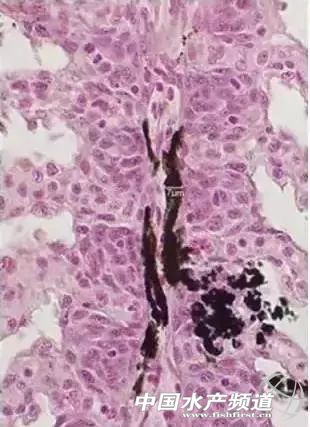

目前,多数鳃霉病的诊断错误是把显微镜下见到的黑色素细胞当做鳃霉菌而误诊。当鱼类在患病状态、亚健康状态或者在各种应激状态下都能在显微镜下见到鳃丝上有大量的黑色素细胞,主要分布在鳃丝基部,有时肉眼可见鳃丝基部发黑,当鱼类恢复健康以后或者应激因素消失以后,在显微镜下也见不到色素细胞。

很多人肉眼见到养殖鱼类鳃丝溃烂或其它异常时,显微镜镜检鳃丝看到黑色素细胞经常误认为是鳃霉菌丝,而错误地诊断为鳃霉病。实际上黑色素细胞与鳃霉菌丝在形状上和大小上都有很大的区别。

鳃丝上的黑色素细胞在显微镜下一般呈类似雪花一样的星芒状,树突状分支很多(如图)

黑色素细胞分枝“纤细”,鳃组织切片观察分枝宽度一般不超过7μm,细胞中的色素颗粒不足1μm,色素颗粒必须在高倍镜下才能见到(如图)。

而鳃霉菌丝“粗壮”,目前国内发现的2种类型的鳃霉,即血鳃霉和穿移鳃霉的菌丝直径分别为8~36μm和7.4~9.6μm,菌丝内的孢子也很大,直径分别为6.6~21.6μm和4.8~9.0μm,菌丝内的孢子在低倍显微镜下即可看到;黑色素细胞在显微镜下一直呈黑色,而鳃霉菌丝呈半透明,特别是把视野调亮时更明显。通过镜检比较很容易区分鳃丝上的黑色素细胞和鳃霉菌丝。